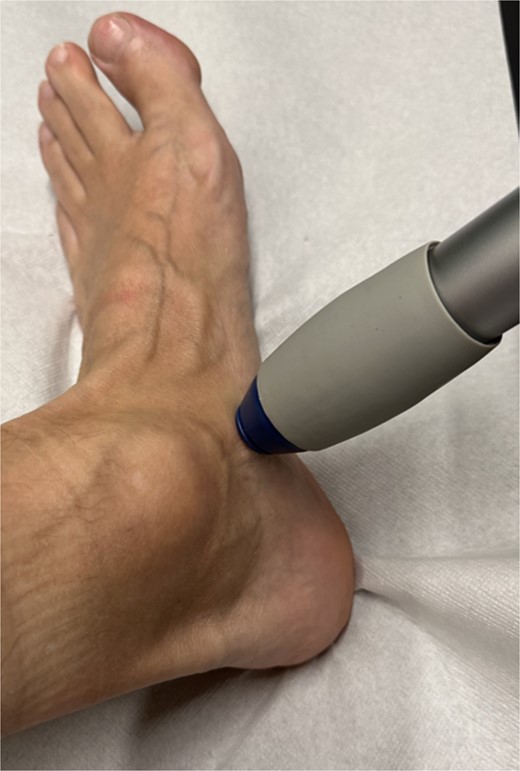

Subsequently, five sessions of extracorporeal radial shock wave therapy at 3-day intervals, each with 4000 impulses, 1 bar, 20 Hz (STORZ MEDICAL, Duolith SD1) were administered (Fig. 4), resulting in significant and sustained pain relief.

Illustration of the technical implementation of extracorporeal shockwave therapy.